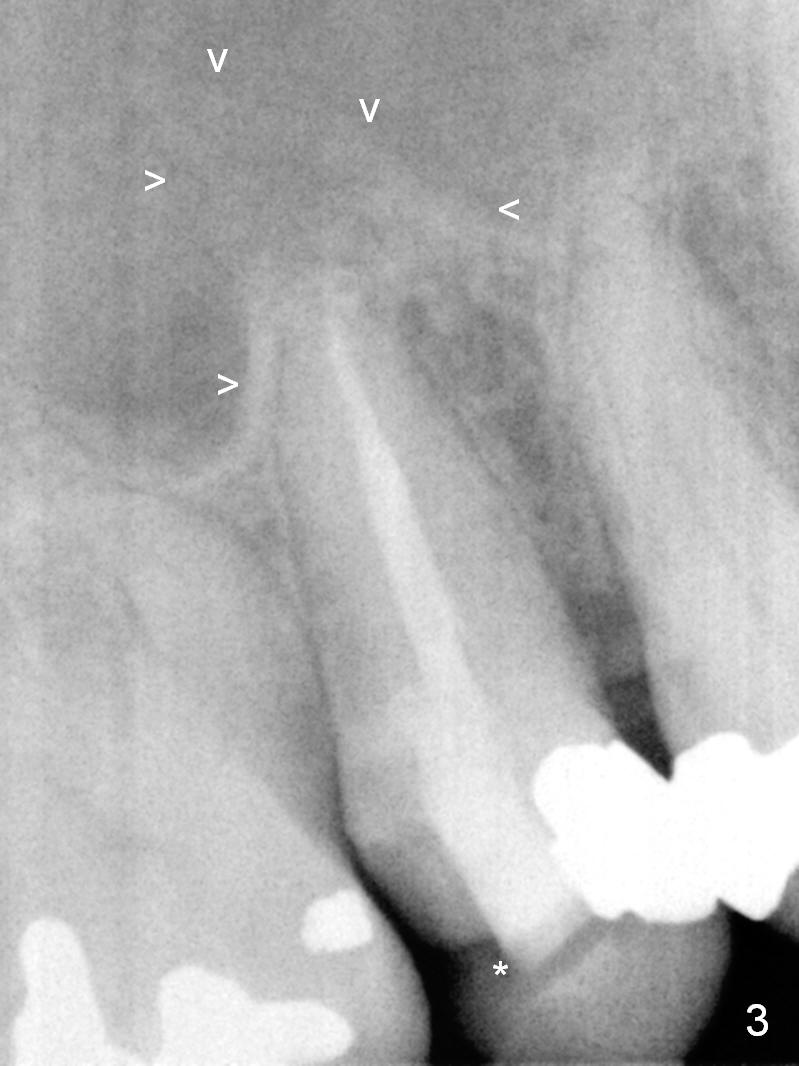

A 55-year-old man had 2nd caries with pulpitis at the tooth #4 a year ago (Fig.1), requiring RCT (Fig.2). The tooth fractured biting on a piece of nut shell inside a moon cake recently (Fig.3 *, 5, 6). There is a sinus septum apical to the apex of the affected tooth (Fig.1-3 arrowheads). After extraction and Metronidazole socket treatment, an immediate implant can be inserted into the septum for primary stability (Fig.4). The diameter of the implant will be decided by the measurement of the mesiodistal width of the root. Magic Expander (ME 3.0 mm) will be used to initiate osteotomy by going deep 4 mm, followed by ME 3.3 mm). If there is resistance to the 1st ME, use 1.6 mm drill. Allograft will be pushed upward with ME 3.3 mm prior to implant placement. Or try to insert (without tapping) ME 4.8 mm as deep as possible, hopefully with stability, and take PA. Place a larger implant for primary stability (4.5x11 mm).